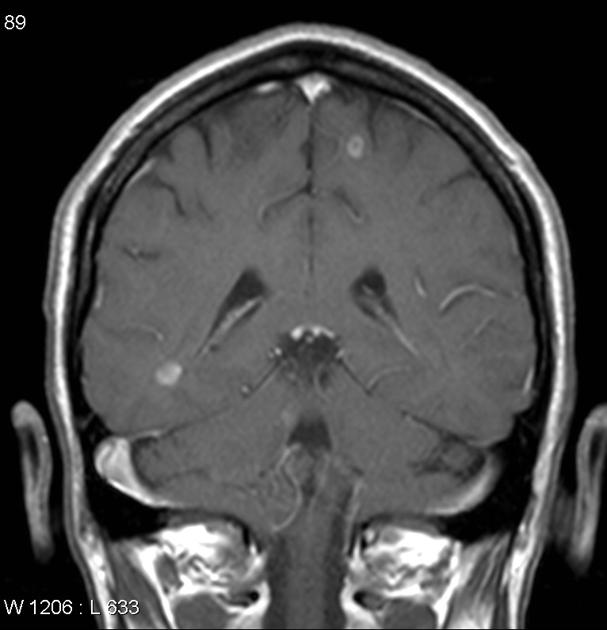

- MRI of the brain and spinal cord (with contrast)